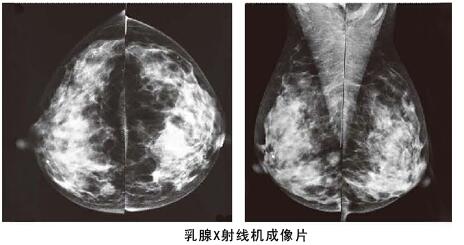

不管是年輕女性,還是已婚媽媽,我們對(duì)于乳腺健康一定要重視,尤其是本身患有乳腺疾病的人,定期去醫(yī)院進(jìn)行乳腺方面的常規(guī)檢查必不可少。目前常規(guī)的乳腺檢查方式一是乳腺彩超,二是利用數(shù)字化鉬靶乳腺機(jī)檢查,這兩種不同的方式,哪種檢查乳腺會(huì)比較好呢?除了常規(guī)的檢查之外,我們還可以采取哪些預(yù)防乳腺疾病的措施呢?

其實(shí)相比乳腺彩超,利用數(shù)字化鉬靶乳腺機(jī)對(duì)于乳腺管較細(xì)或者乳腺本身存在問題,可以進(jìn)行更加細(xì)致檢查,而且它是女性乳腺癌早期診斷的金標(biāo)準(zhǔn),數(shù)字化鉬靶乳腺機(jī)可以發(fā)現(xiàn)0.1毫米的鈣化點(diǎn),提示癌前病變。是各種乳腺疾病檢查的必備醫(yī)療設(shè)備:如乳腺炎癥,乳腺增生,乳腺纖維瘤,乳腺囊腫等。對(duì)于一些年齡較大的女性來說,數(shù)字化鉬靶乳腺比乳腺彩超檢查更加的準(zhǔn)確。